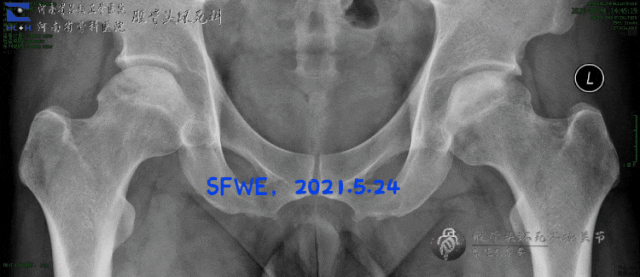

X光片看上去就有点严峻:双侧坏死的面积较大,所幸还没有塌陷。